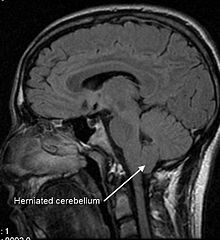

Therefore, we call disc herniation the degeneration, displacement and exit of the vertebral disc, almost always with injury and rupture of its structure, out of its place, usually giving rise to an affectation of neighboring structures.

It is accompanied by inflammation and pain of the structures of the vertebral canal: the spinal cord, the meninges, the cauda equina in the lumbar levels or also, the roots and dorsal ganglia that come out of the spine through the holes of conjunction.

Complementary imaging tests, such as magnetic resonance imaging, are excellent tools that allow us to specify the origin of a problem but, as we like to repeat, «we do not treat complementary tests, we do not treat MRIs, we treat patients», that is, It is the symptoms, the patient’s complaint that makes us seek treatment.